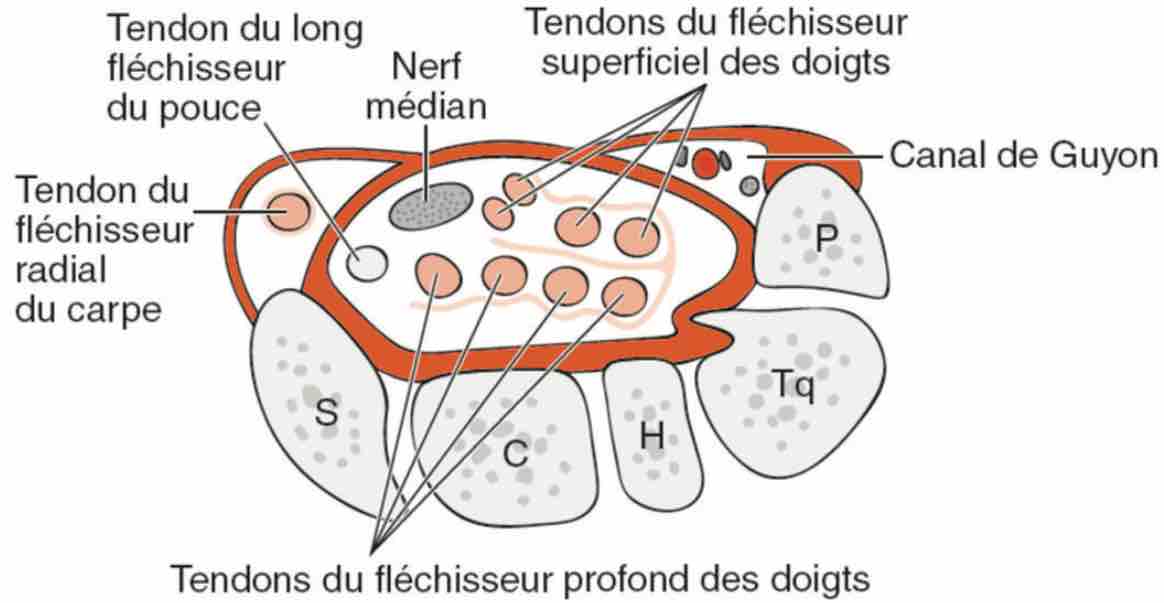

sd canal carpien = nerf > 12-15 mm², index d'aplatissement > 3,

sd canal carpien = nerf > 12-15 mm², index d'aplatissement > 3,nerf hypo +/- signal Doppler, bombement rétinaculum > 4 mm,

Pas d'anomalie des nerfs médian et ulnaire au poignet.